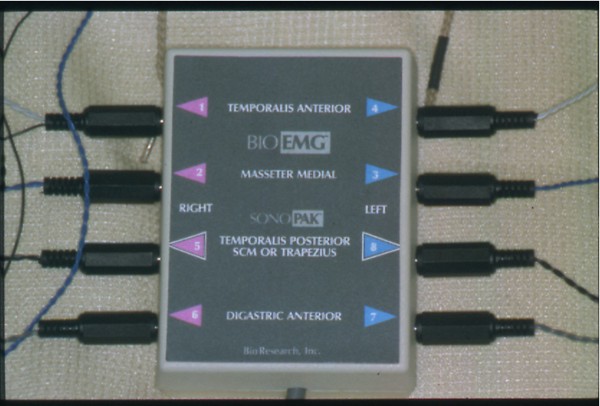

Bio Pack

Fig.6

Sensores Electromiográficos

Bio Pack

Fig.7

Receptor electromiográfico

Bio Pack

Fig.8

Magneto detector del

Movimiento

Bio Pack

Fig.9

Bobinas captoras del

Movimiento del magneto